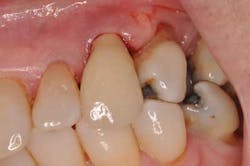

A new patient presents to my office with a chief complaint: “My implant crown fell off yesterday.” She’s a 72-year-old woman with noncontributory medical history. She states the implant in tooth position No. 11 was placed “a few years ago and never felt right.” Examination reveals a prefabricated abutment of some sort that is not mobile. Curiously, the peri-implant gingiva has a slight erythema. Moderate bleeding is noted upon insertion of the implant crown.

Fig. 1: Implant crown seated.

Fig. 2: Moderate bleeding noted around prefabricated abutment after crown is removed.